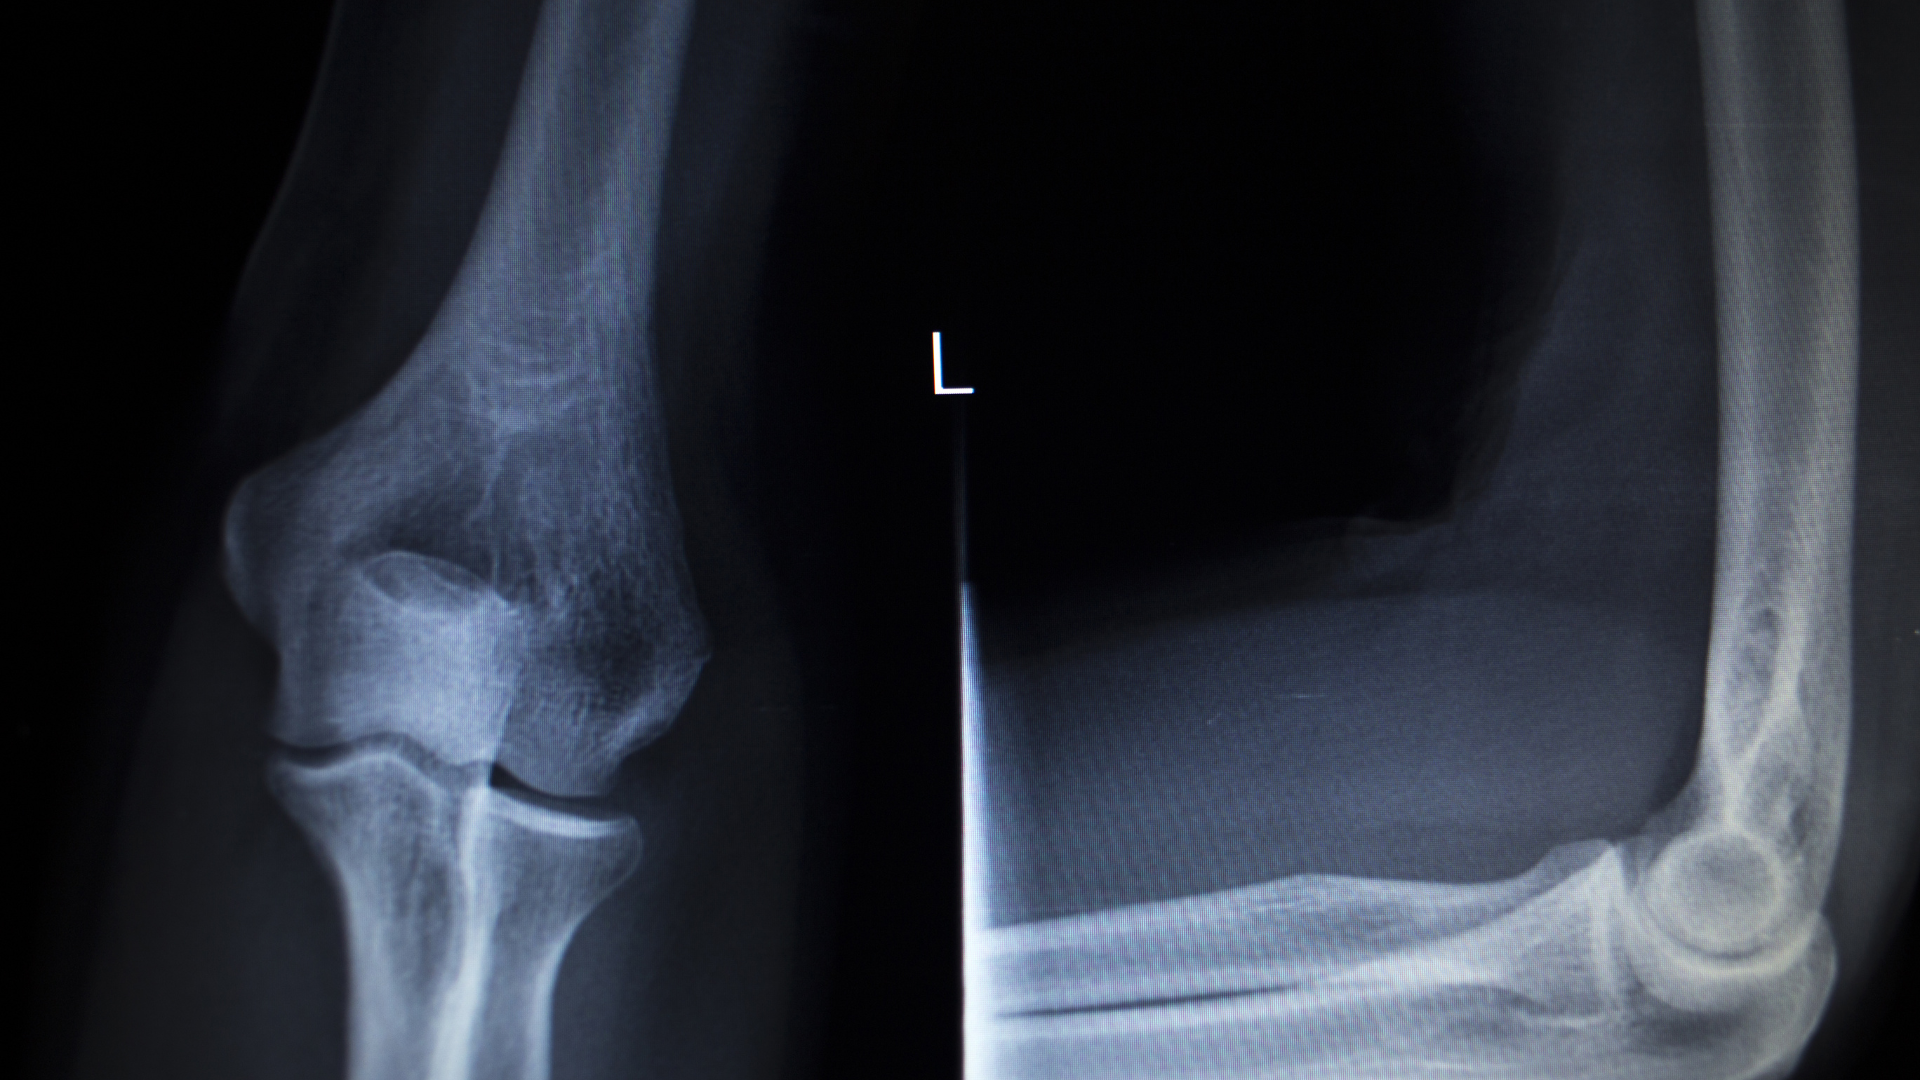

Các tư thế chụp thường gặp

Để đánh giá chính xác, kỹ thuật viên có thể yêu cầu thực hiện nhiều tư thế:

- Tư thế thẳng.

- Tư thế nghiêng.

- Tư thế chếch.

Việc thay đổi góc chụp giúp quan sát rõ hơn cấu trúc khớp và phát hiện bất thường.

Hình ảnh bình thường

Một phim X-quang khớp khuỷu bình thường thường có:

- Cấu trúc xương rõ nét.

- Khe khớp đều.

- Không có dấu hiệu lệch trục.

Dấu hiệu bất thường

Một số dấu hiệu có thể gợi ý vấn đề:

- Xuất hiện đường gãy.

- Lệch vị trí khớp.

- Hẹp khe khớp.

- Hình thành gai xương.